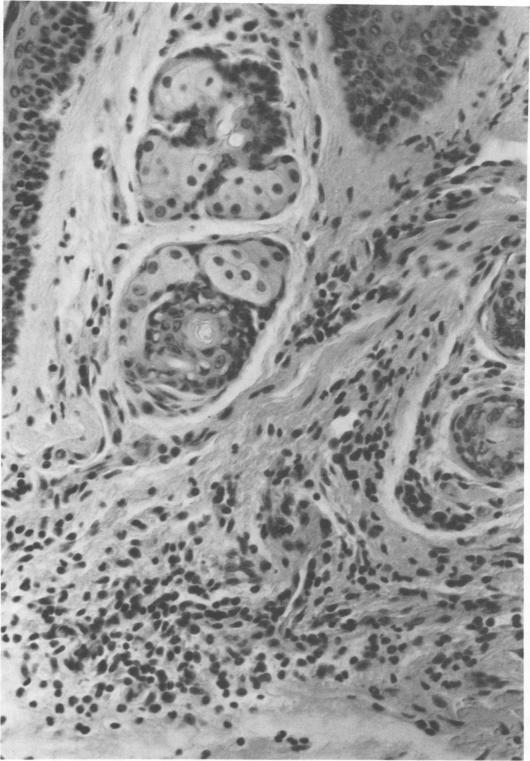

Various preparations of Mycobacterium lepraemurium were used to elicit delayed-type hypersensitivity in the footpad of mice infected with this organism. With a sonicated preparation of the mycobacterium, a significant increase in footpad swelling was elicited in mice infected with M. lepraemurium 5 weeks previously, but not in BCG-infected animals or uninfected controls. This footpad reaction was shown to peak at 24 h and to be associated with an infiltration of mononuclear cells. The kinetics of footpad swelling, its association with lymphoproliferation, and its dependence on T lymphocytes were each examined. The results support the hypothesis that this is a delayed-type hypersensitivity reaction. The ability to transfer this reactivity to normal mice with cells but not serum offers further confirmation that this hypersensitivity is dependent on cell-mediated immunological mechanisms rather than humoral antibody. The relevance of this to the study of the immunological response of mice to murine leprosy is discussed.

使用多种鼠麻风分枝杆菌制剂在感染该病原体的小鼠足垫中引发迟发型超敏反应。用该分枝杆菌的超声破碎制剂,在5周前感染鼠麻风分枝杆菌的小鼠中引发了足垫肿胀的显著增加,但在卡介苗感染的动物或未感染的对照中未出现这种情况。这种足垫反应在24小时达到峰值,并与单核细胞浸润有关。分别检查了足垫肿胀的动力学、其与淋巴细胞增殖的关联以及其对T淋巴细胞的依赖性。结果支持这是一种迟发型超敏反应的假设。用细胞而非血清将这种反应性转移到正常小鼠的能力进一步证实了这种超敏反应依赖于细胞介导的免疫机制而非体液抗体。讨论了这与小鼠对鼠麻风免疫反应研究的相关性。